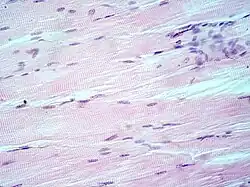

Hematoxylin and eosin stain (or haematoxylin and eosin stain or hematoxylin–eosin stain; often abbreviated as H&E stain or HE stain) is one of the principal tissue stains used in histology.[1][2][3] It is the most widely used stain in medical diagnosis[1] and is often the gold standard.[4] For example, when a pathologist looks at a biopsy of a suspected cancer, the histological section is likely to be stained with H&E.

H&E is the combination of two histological stains: hematoxylin and eosin. The hematoxylin stains cell nuclei a purplish blue, and eosin stains the extracellular matrix and cytoplasm pink, with other structures taking on different shades, hues, and combinations of these colors.[5][6] Hence a pathologist can easily differentiate between the nuclear and cytoplasmic parts of a cell, and additionally, the overall patterns of coloration from the stain show the general layout and distribution of cells and provides a general overview of a tissue sample's structure.[7] Thus, pattern recognition, both by expert humans themselves and by software that aids those experts (in digital pathology), provides histologic information.

Hematoxylin principally colors the nuclei of cells blue or dark-purple,[6][15][14] along with a few other tissues, such as keratohyalin granules and calcified material. Eosin stains the cytoplasm and some other structures including extracellular matrix such as collagen[5][7][14] in up to five shades of pink.[8] The eosinophilic (substances that are stained by eosin)[5] structures are generally composed of intracellular or extracellular proteins. The Lewy bodies and Mallory bodies are examples of eosinophilic structures. Most of the cytoplasm is eosinophilic and is rendered pink.[10][15] Red blood cells are stained intensely red.

The structures do not have to be acidic or basic to be called basophilic and eosinophilic; the terminology is based on the affinity of cellular components for the dyes. Other colors, e.g. yellow and brown, can be present in the sample; they are caused by intrinsic pigments such as melanin. Basal laminae need to be stained by PAS stain or some silver stains, if they have to be well visible. Reticular fibers also require silver stain. Hydrophobic structures also tend to remain clear; these are usually rich in fats, e.g. adipocytes, myelin around neuron axons, and Golgi apparatus membranes.